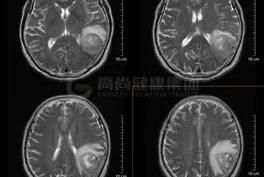

【高尚病例】脑膜瘤

2026-02-11